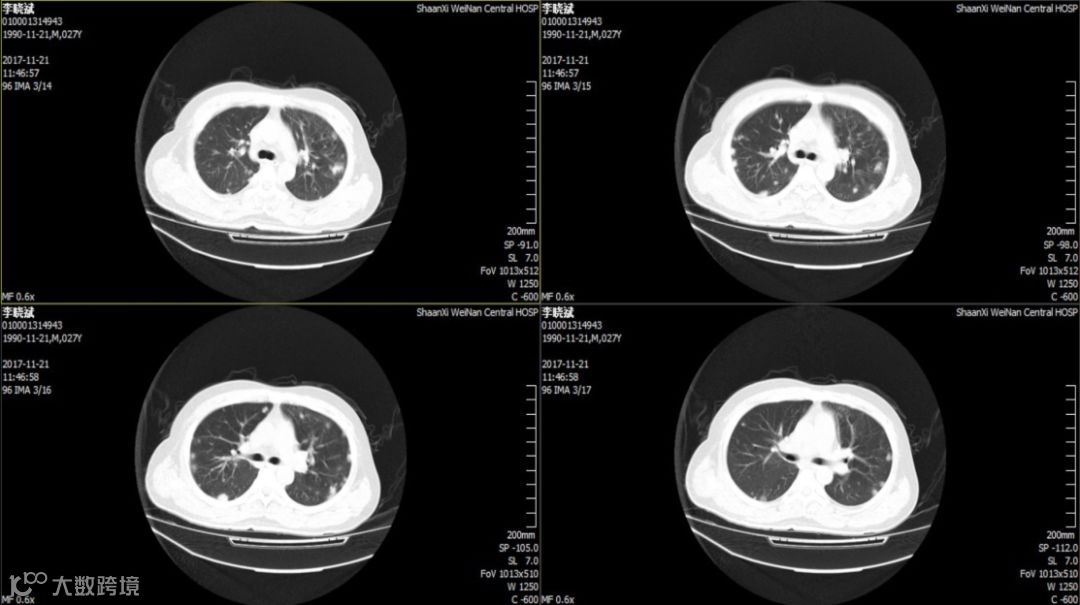

入院后第2天胸腹部CT:双肺所见,考虑特殊菌感染可能,腹腔少许游离气体,肝右叶混杂密度包块。

血培养:肺炎克雷伯杆菌亚型,常用药物均敏感。

2018.11.25复查CT:双肺炎症,考虑特殊细菌感染可能,双侧胸膜腔少量积液,心包少量积液,腹腔少量积液,少许游离气体,部分包裹,肝右叶、脾实质混杂密度包块,脓肿并气体。因经济原因换用头孢曲松 2.0 g,QD,ivgtt。12月8日再次发热,12月12日肝脏穿刺引流后体温逐渐正常,CT提示病灶逐渐吸收。